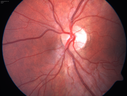

16 year old with incidental finding of retinal AV malformation but vision in the left eye is not as good as the right eye. VA OD: sc20/16 NscJ1+ VA OS: sc20/20-1 NscJ1+